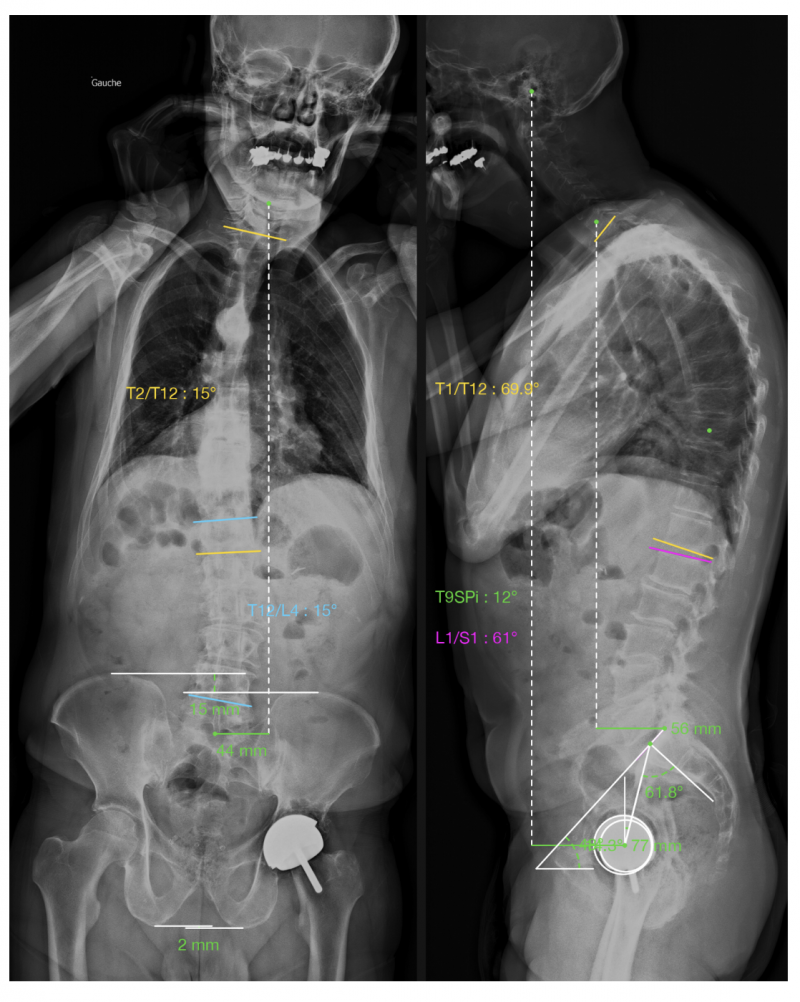

L’un des principes fondateurs de l’EOS est la possibilité de relier, sur une même image, la statique rachidienne, la position du bassin et les axes des membres inférieurs. L’examen devient ainsi un outil d’analyse biomécanique globale.Figure 4: Exemple de livret résumé réalisé à l’aide d’un algorithme d’Intelligence Artificielle (correspondant aux mesures en Figure 3).

Toutefois, il n’est pas rare que l’IA fasse des erreurs de mesure, nécessitant une correction manuelle par le manipulateur et le radiologue.Dans la scoliose idiopathique de l’adolescent, l’EOS a d’abord été adopté pour sa faible irradiation: il permet un suivi rapproché sans exposition excessive. Mais son apport va bien au-delà : les reconstructions permettent de mesurer la déviation frontale (angle de Cobb), la rotation vertébrale et les courbures sagittales réelles. L’analyse globale révèle parfois des déséquilibres compensateurs mal appréciés sur les clichés classiques. Cette précision favorise une meilleure adaptation des corsets et une planification chirurgicale plus fine. L’analyse rachidienne de l’adolescence doit toujours être conjointe avec le stade d’ossification selon Risser.Pour la scoliose de l’adolescent, la mesure clé reste l’angle de Cobb : une valeur ≥ 10° définit la scoliose. En-dessous, on parle plutôt d’attitude scoliotique, souvent posturale. Le niveau de rotation doit également être apprécié. Concernant les indications thérapeutiques, la surveillance simple est habituellement recommandée pour une scoliose inférieure à 20-25°. Le corset est recommandé en cas d’angle de Cobb entre 20 et 40° chez des adolescents avec un stade de Risser de 0 à 3. La rééducation spécifique est indiquée chez ces adolescents, ainsi que chez les adolescents avec un angle de Cobb entre 25 et 40° et un stade de Risser 4-5. La chirurgie doit être discutée pour un angle de Cobb supérieur à 40-45° chez un adolescent encore en croissance. Ces repères sont issus des recommandations internationales SRS.Figure 5: Exemple d’analyse globale d’un déséquilibre rachidien coronal et sagittal de l’adulte

Chez l’adulte, l’EOS s’est imposé dans l’étude de l’équilibre sagittal, devenu un élément central de la prise en charge des lombalgies chroniques et des déformations dégénératives. Trois paramètres résument cet équilibre : la distance sagittale entre la vertèbre C7 et le sacrum (SVA), la bascule pelvienne (pelvic tilt) et la différence entre l’incidence pelvienne et la lordose lombaire (IP – LL). Les valeurs de référence sont bien établies : le SVA doit normalement être inféieur à 25 mm et l’écart IP–LL inférieur à 10° pour traduire une statique sagittale harmonieuse. Au-delà, le déséquilibre devient cliniquement significatif ; le patient compense par une rétroversion du bassin ou une flexion des genoux, souvent sources de douleurs et de fatigue posturale. Quand ces valeurs sont inadéquates, elles sont associées, dans la population générale, à une perte de qualité de vie, de fonction et à une augmentation des douleurs.Une séquence habituelle de décompensation sagittale est la perte de la lordose lombaire en rapport avec l’arthrose (IP-LL), s’accompagnant ensuite de compensations: d’abord une extension au niveau thoracolombaire (la colonne thoracique devient plus plate par diminution de la cyphose), puis par une rétroversion du bassin (équivalent à une extension de hanche) puis une flexion des genoux. Au niveau cervical, l’objectif est de maintenir un regard horizontal, par augmentation de la lordose cervicale. L’intérêt de l’EOS est de quantifier ces phénomènes en position debout, donc dans des conditions fonctionnelles. Dans le cadre des chirurgies de ré-équilibrage sagittal, la mesure préopératoire de ces paramètres permet d’anticiper le degré de correction nécessaire et d’évaluer le résultat post-opératoire avec une bonne reproductibilité.Au-delà du rachis, l’EOS a trouvé sa place dans l’analyse du bassin et des membres inférieurs. L’examen en charge révèle les interactions entre la morphologie pelvienne, les axes mécaniques des fémurs et des tibias, et la répartition du poids corporel. On peut mesurer les angles de varus ou de valgus, les torsions fémorales et tibiales et surtout les inégalités de longueur des membres. Une différence de 10 mm ou plus est généralement considérée comme cliniquement significative : elle peut s’associée à une bascule pelvienne voir une scoliose compensatrice.En-dessous de cette valeur, les compensations musculaires suffisent la plupart du temps ; au-delà, une correction par semelle peut être indiquée, et lorsque l’écart dépasse deux centimètres, la discussion chirurgicale peut se poser.Dans la planification des prothèses de hanche et de genou, l’EOS offre un avantage décisif : il permet de mesurer les paramètres d’orientation en position fonctionnelle. Les planifications effectuées à partir de scanners en décubitus ne reflètent pas la réalité dynamique du patient ; l’EOS comble cette lacune.Figure 6: Exemple d’analyse des membres inférieurs permettant à la fois des mesures d’inégalité de longueur, mais également des analyses angulaires du bassin, des hanches, des genoux, et de la statique globale des membres inférieurs de face et de profil.